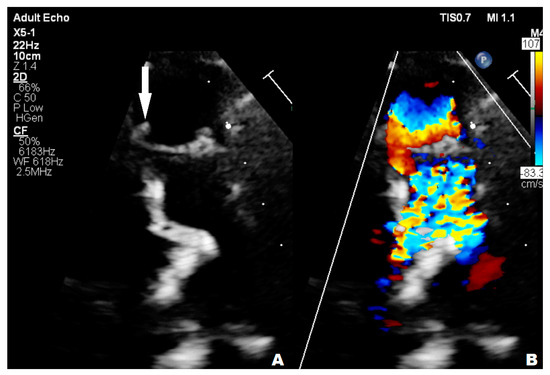

3.1. Case 1

3.2. Case 2

3.3. Case 3

3.4. Case 4